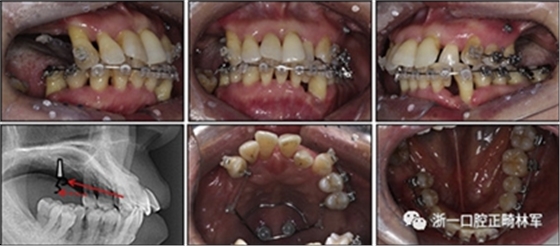

對于近中傾斜和過度萌出的上頜右側尖牙,需要控制牙齒向遠中傾斜和向下推入。用兩個鉤子在兩側施加不同方向的力,以期望右側尖牙的推入(圖7)。在上頜尖牙遠中移動后,用一根0.014英寸的鎳鈦弓絲將4顆上頜前牙排齊。放置逐漸變硬的弓絲,直到上下兩個牙弓都放置0.017*0.025英寸的不銹鋼弓絲。

然后關閉下頜前牙區(qū)間隙,用完全相同的力學原理將上頜全牙列向遠中移動,以獲得適當?shù)母埠虾透采w。此外,還有一個0.017*0.025英寸β-鈦絲的直立彈簧應用于下頜右側第二磨牙。當直立彈簧接合到主弓絲上時,引起前磨牙的推入,第二磨牙的推出,前磨牙的頰側傾斜以及第二磨牙的舌側傾斜,以矯正牙弓形態(tài)(圖8)。

圖7. 用TAD將上頜牙齒推向遠中。兩個附著在TAD上不同方向的鉤子

由于患者有多個缺失的后牙,因此考慮到具有垂直方向的喪失。然而,她在拔除后牙后立即去正畸科就診。她封閉了天然的左側前磨牙,并且沒有前牙的咬合磨損。因此,垂直維度被維持是確定的。在正畸治療過程中,牙種植體植入在上頜后牙區(qū)和下頜右側第一磨牙的位置(圖9)。

經(jīng)過3個月的骨結合后,種植體用臨時冠修復以支持垂直維度。

圖9. 上頜牙齒推向遠中,糾正下頜左側磨牙的傾斜度,并放入種植體